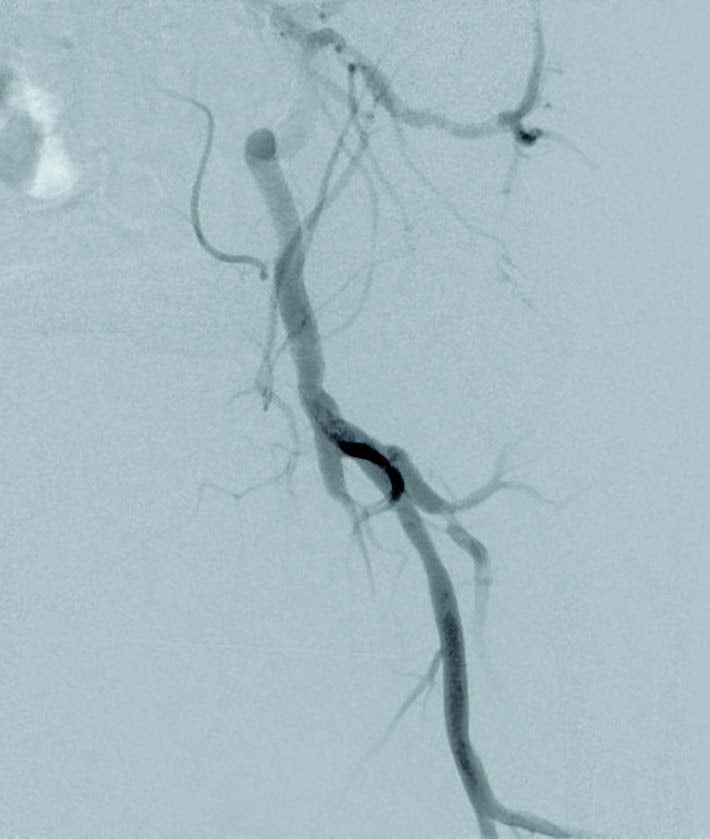

当症例は、20 cmを超える浅大腿動脈長区域病変(図1)である。一般的に、バルーンでの拡張後の解離が修復できなかったり、プラークの圧着が不充分な場合には、ステントなどのスキャフォルドが必要になる。治療当時はベアメタルステントの成績も期待が持てず、薬剤溶出型ステント(DES)の成績も未知数であったが、ゴア® バイアバーン® ステントグラフトに関しては、唯一20 cm以上の病変長でも適応があり、25 cmまでの長区間病変での成績1,2も発表されているので、成績に期待が持てた。

当症例の悩ましいポイントは、バイアバーン® ステントグラフトの適切な留置時ポイントの一つがヘルシーランディングを行うことであるが、造影上CTO病変遠位部に発達したコラテラル血管があり、そのコラテを温存してバイアバーン® ステントグラフトをヘルシーランディングできるかどうかであった。

当院では、通常IVUSと造影で閉塞部両端のプラークの少ない健常部と思われる部分をマーキングし、ヘルシーランディングのポイントをIVUSを用いて確認している。この時、メジャーを貼っておいて位置確認に使用すると位置のずれを気にせず作業できる。当症例では、コラテ(図1矢印①)を温存しながら、ヘルシーランディングを行う戦略とし、前拡張を行うこととした。また、IVUSで計測された血管径から至適と思われるサイズ(遠位健常部の血管径が一つの目安になる)のバルーンにて前拡張を行うことにしており、バルーンの径サイズは遠位健常部の血管径に合わせると余計な解離なく拡張できると考え、また、バイアバーン® ステントグラフトを使用する場合には、5 mm以上のバルーンサイズで拡張できるか検討することにしている。さらに、200-300 mm長のロングバルーンで1-2回の長時間拡張(当院では3-5分)を行うと期待する拡張が得られやすいと考えており、当症例では、径6.0/長300 mm セミコンプライアントバルーンで前拡張を行った。

前拡張後の造影で温存したいコラテ部分に解離が認められ(図2)、また、IVUSでヘルシーランディングが可能な位置を確認したところ、遠位部のコラテ(図1矢印②)を温存してヘルシーランディングができることを確認できた。さらにIVUSで血管径を確認し、同等サイズのバイアバーン® ステントグラフトを留置した。バイアバーン® ステントグラフトが展開し始めた後、展開ラインをゆっくり連続した動作で引くようにするとバイアバーン® ステントグラフトの位置がずれることなく留置することが可能であった。その後、バイアバーン® ステントグラフト全長を同径のバルーンで高圧後拡張してIVUSでバイアバーン® ステントグラフトが充分拡張されていることを確認し、手技を終了した。(図3)

当症例は比較的石灰化の少ない長区間のCTO症例であり、臨床成績の観点や長さ20 cm以上の病変に対しても薬事適応が認められているデバイスであるという観点もふまえて、バイアバーン® ステントグラフトを選択した。当症例において、IVUS所見からは血管径が6.0 mmあり小血管ではないことや、留置位置となるレファレンス上下ともヘルシーランディングが可能かを確認したうえで、バイアバーン® ステントグラフトを留置した。コラテラル血管の温存が悩ましい症例であったが、より遠位部のコラテラル血管も温存できることもあり、ヘルシーランディングを重視し、コラテ血管をバイアバーン® ステントグラフトでカバーし、病変をフルカバーすることで再狭窄の懸念も少なく、長期予後を期待できると考えた。